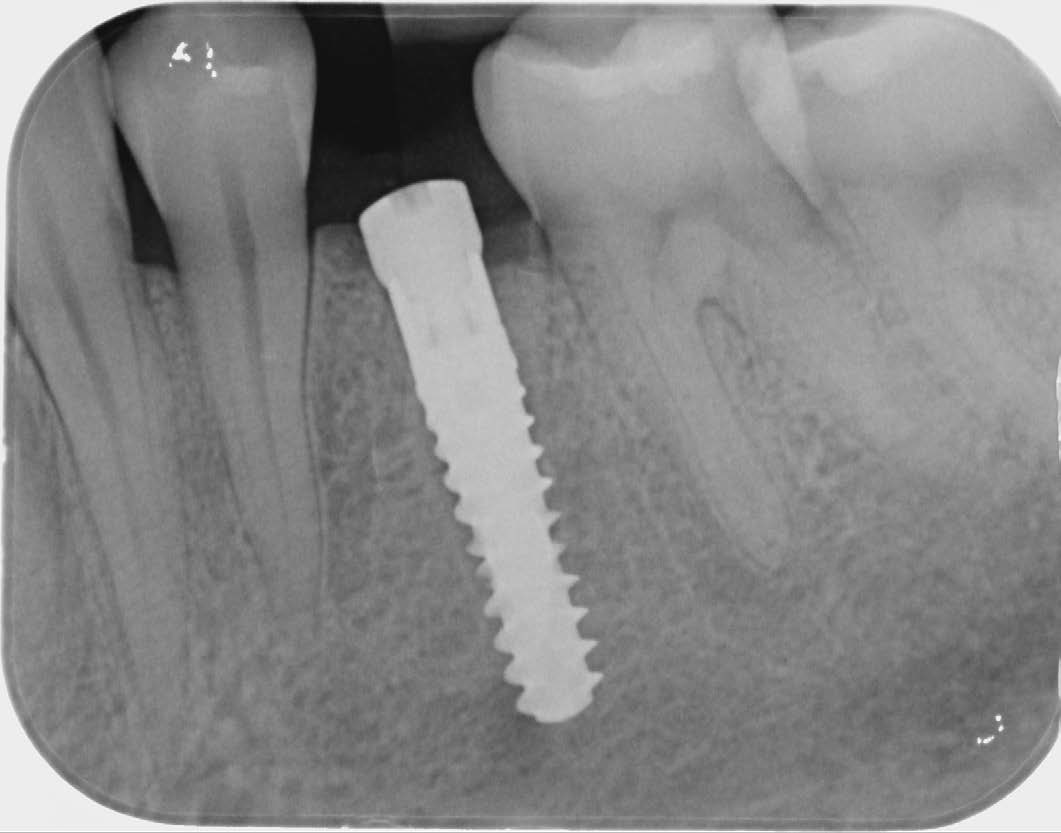

Fig. 6: Postoperative X-ray image of region 34, condition after immediate implantation. |

I chose the Socket Shield Technique, a minimally invasive method to reduce tissue shrinkage and achieve better long-term aesthetic outcomes. The technique requires healthy periodontal tissue and an intact root, both of which were present. The tooth is partially extracted, leaving the buccal root portion to support the soft tissue. This maintains the buccal periodontal attachment, allowing the tissue to behave as if the tooth were still in place. Hürzeler et al. introduced this technique in 2010 to reduce tissue shrinkage during immediate implantation.

After osteotomy, I placed a 3.75 mm diameter implant, filled the gap between implant and root surface with allogenic bone substitute, inserted a provisional, and later restored with an aesthetic ceramic crown.